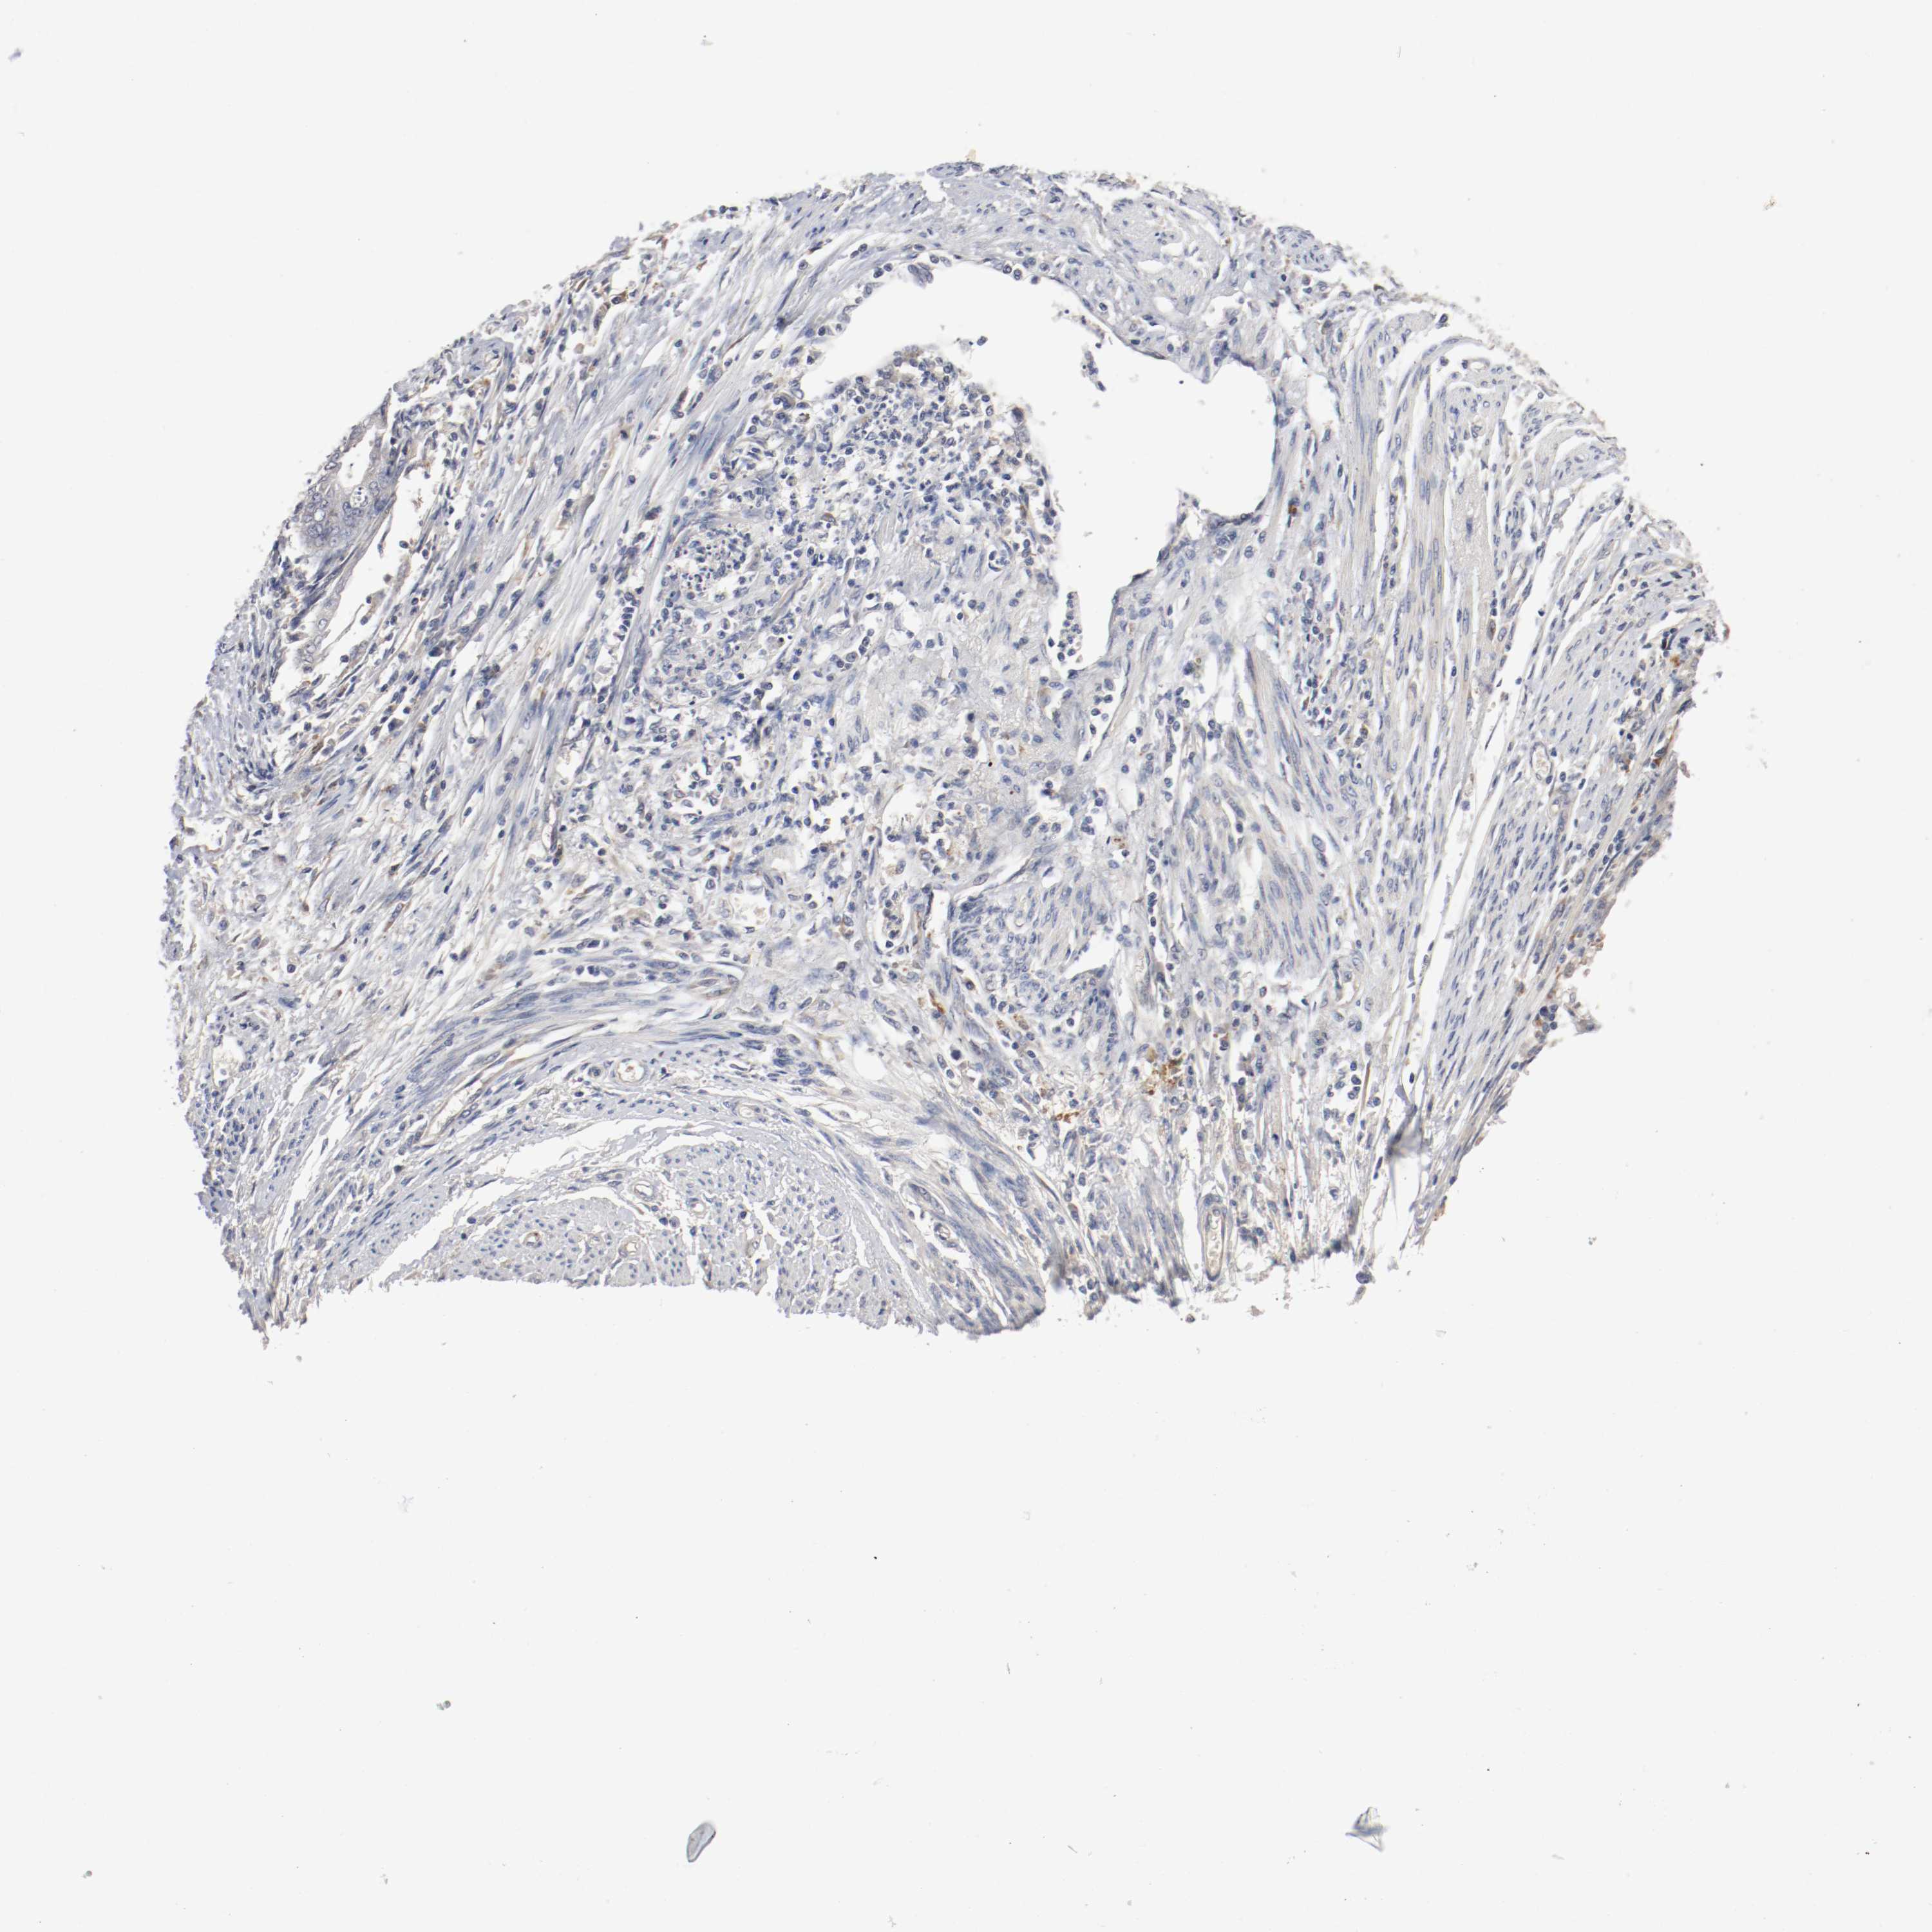

ENDOMETRIAL CANCER - Protein expressioni

A mouse-over function shows sample information and annotation data. Click on an image to view it in a full screen mode. Samples can be filtered based on level of antibody staining by selecting one or several of the following categories: high, medium, low and not detected. The assay and annotation is described here.

Note that samples used for immunohistochemistry by the Human Protein Atlas do not correspond to samples in the TCGA dataset.

Antibody stainingi

Antibody staining in the annotated cell types in the current human tissue is reported as not detected, low, medium, or high, based on conventional immunohistochemistry profiling in selected tissues. This score is based on the combination of the staining intensity and fraction of stained cells.

Each image is clickable and will lead to virtual microscopy that enables deeper exploration of all samples and also displays staining intensity scores, fraction scores and subcellular localization as well as patient and tissue information for each sample.

Antibody HPA005131

Staining

High

Medium

Low

Not detected

Intensity

Strong

Moderate

Weak

Negative

Quantity

>75%

75%-25%

<25%

None

Location

Nuclear

Cytoplasmic/membranous

Cytoplasmic/membranous,nuclear

Adenocarcinoma, NOS

Neoplasm, malignant, NOS